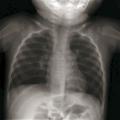

Radiographie thoracique :

– réservée aux formes sévères hospitalisées ou d’évolution inhabituelle (fébrile ou traînante) :

– « syndrome bronchique » ;

– distension avec hyperclarté des 2 champs pulmonaires, horizontalisation des côtes (plus de 9 espaces intercostaux visibles) et aplatissement des coupoles diaphragmatiques (fig. 1) ;

– atteinte alvéolaire avec opacités floconneuses périphériques ;

– atélectasie segmentaire ou lobaire en cas de bouchons muqueux (craindre une surinfection bactérienne) [fig. 2] ;

– plus rarement, aspect d’emphysème lobaire, médiastinal ou pneumothorax.